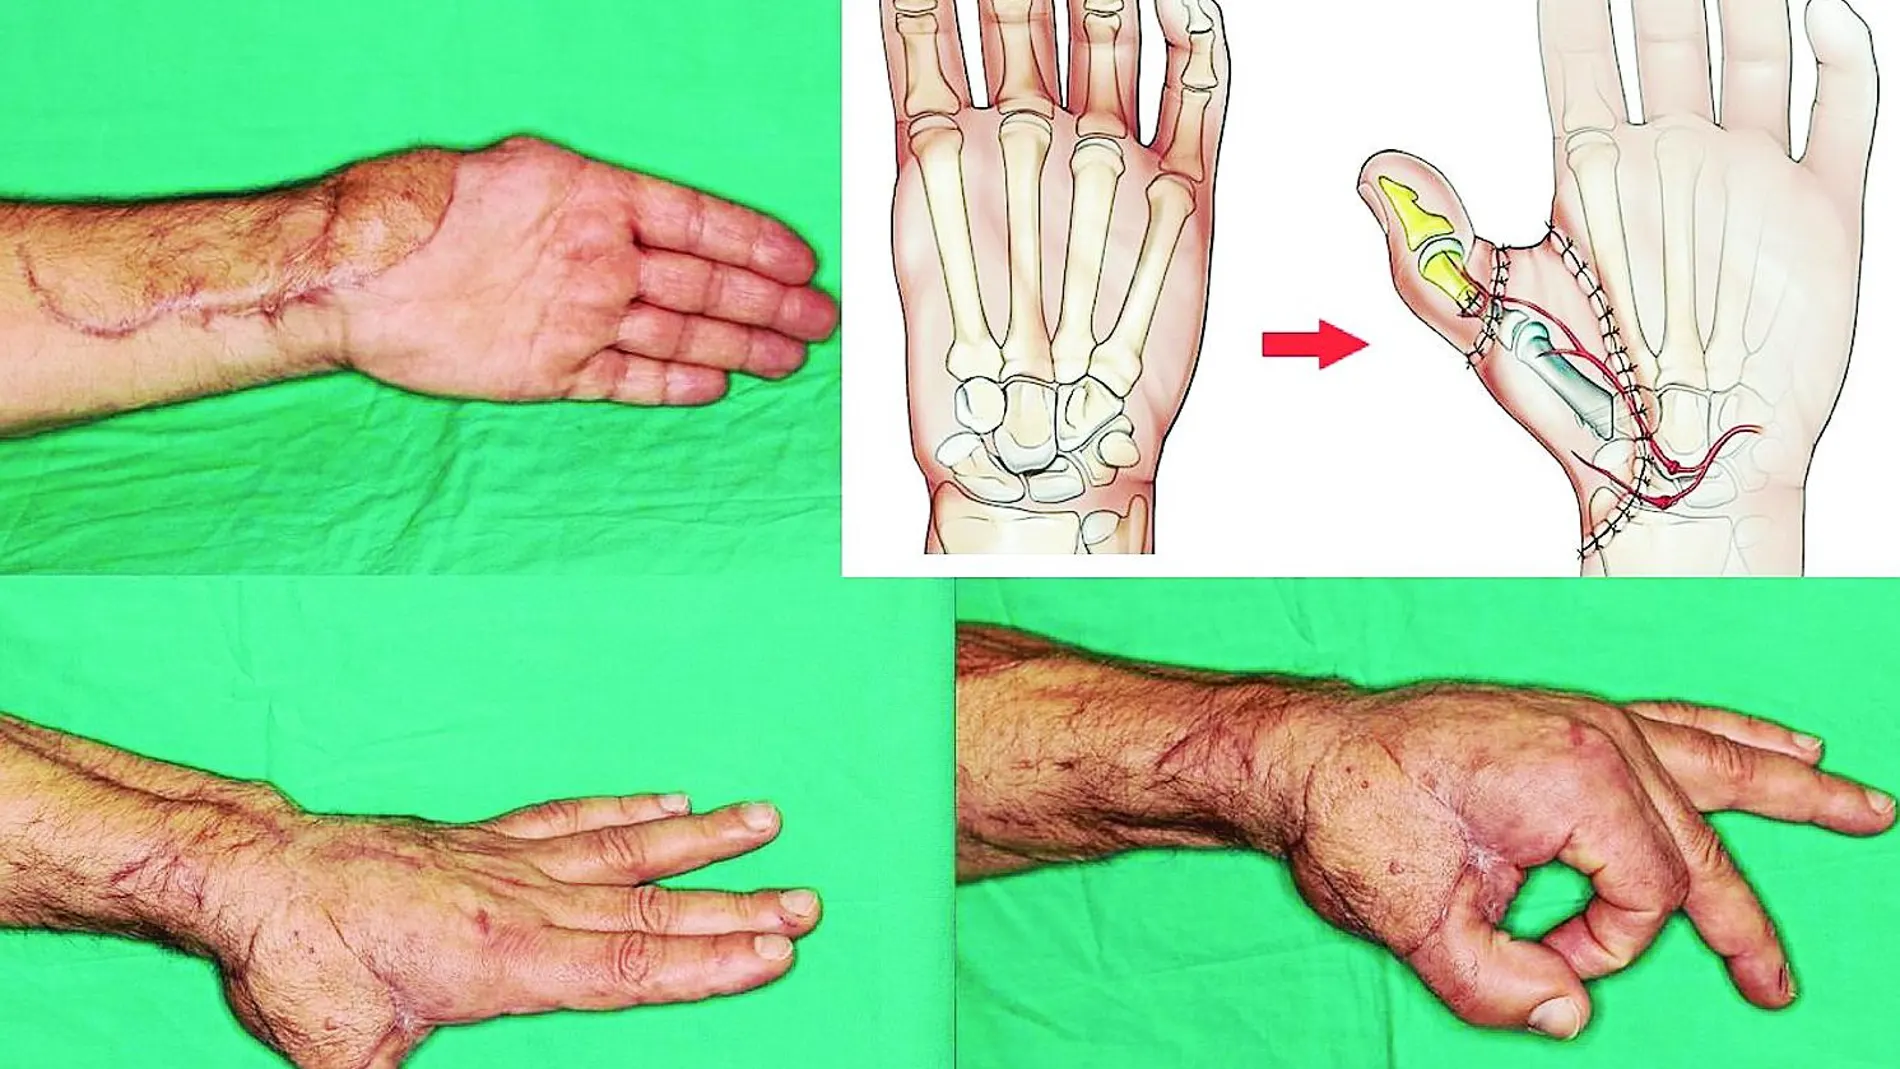

Afortunadamente, un compañero de trabajo le recomendó que acudiese a la clínica del doctor Francisco Piñal. Un cirujano especializado en la cirugía de mano que ha realizado ya más de 500 intervenciones donde trasplanta dedos del pie a la mano. Arreglar su mano no sería fácil. «Todo –explica el doctor Francisco Piñal– estaba al revés. Le habían hecho previamente una serie de cosas que a mí me perjudicaban seriamente la reconstrucción. No sólo había perdido el dedo gordo, sino que también le faltaba un trozo de mano». Aún con todo, era posible. Alfonso aceptó la propuesta del cirujano de implantarle el pulgar del pie a su mano: «No quedaba otra, era la única opción».

Para un cirujano ninguna mano es igual a otra. «Lo más fácil de arreglar son los tendones y los nervios», asevera el doctor Francisco Piñal. Según este especialista, «lo más difícil es conectar las venas y las arterias. Estamos hablando de tuberías de un milímetro de diámetro». En una operación de este tipo no sólo importa recuperar la funcionalidad, sino también lograr una buena estética. «No es un objetivo secundario ni superfluo. Tienes que conseguir una mano que el paciente encuentre como normal, útil y sobre todo que sea aceptable para los demás».

La operación de Alfonso, realizada en el Hospital La Luz de Madrid, se prolongó durante 12 horas y fue todo un éxito. En menos de un año desde la cirugía que el doctor Piñal le realizó, ya estaba incorporado a su puesto de capitán de máquinas en el atunero. A nivel de trasplantes, ya no hay límites para los cirujanos. «Técnicamente podemos conectar lo que queramos, lo que aún queda por mejorar es que cuando nos falta algo tengo que quitarlo de otro sitio del paciente. Para así no recurrir a un donante y evitar la toma de medicación antirrechazo, que hoy en día no es inocua», concluye Francisco Piñal.